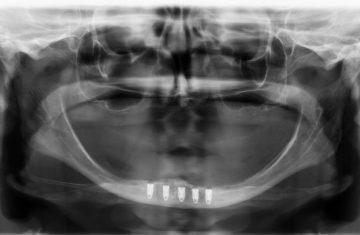

Cirurgia Guiada por Dr. João Marcelo Arcoverde

Adepto à filosofia de trabalho de que menos é mais, Dr. João Marcelo Arcoverde se tornou pioneiro no Brasil ao unir a técnica que permite repor dentes perdidos sem a necessidade de cortes e uso de bisturi convencional que diminuem drasticamente a necessidade de enxertos ósseos.

A Cirurgia Guiada é uma técnica inovadora, cujo implante dentário é feito sem cortes e pontos, portanto gerando maior conforto ao paciente, seja na reposição de um dente, de vários ou de todos.